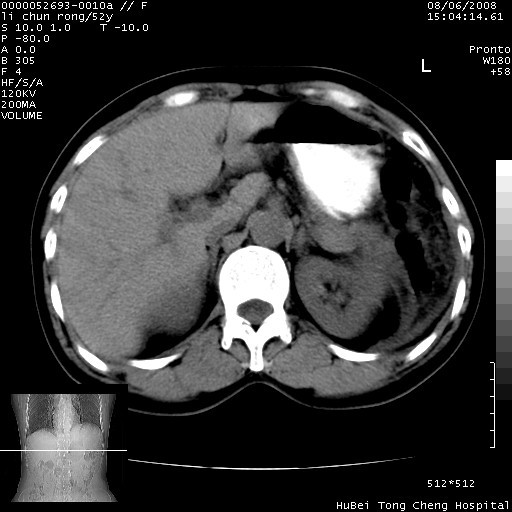

以下是引用云翔在2008-8-7 6:20:00的发言:[br]胰尾部囊性病变,考虑假囊肿,结合实验室检查疾病史

以下是引用zjzjr在2008-8-7 8:38:00的发言:[br]支持胰腺炎伴假囊肿形成,左肾小囊肿.少量腹水.

以下是引用随光逐影在2008-8-7 9:12:00的发言:[br]1)考虑胰腺炎伴假性囊肿形成可能性大;胰腺囊腺瘤待排。2)左肾小囊肿。3)少量腹水。